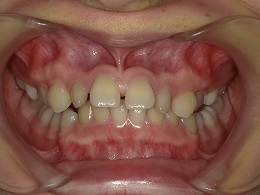

治療中正面

お試し矯正後、深い噛み合わせ改善のため上下全体矯正中の患者様の症例になります。